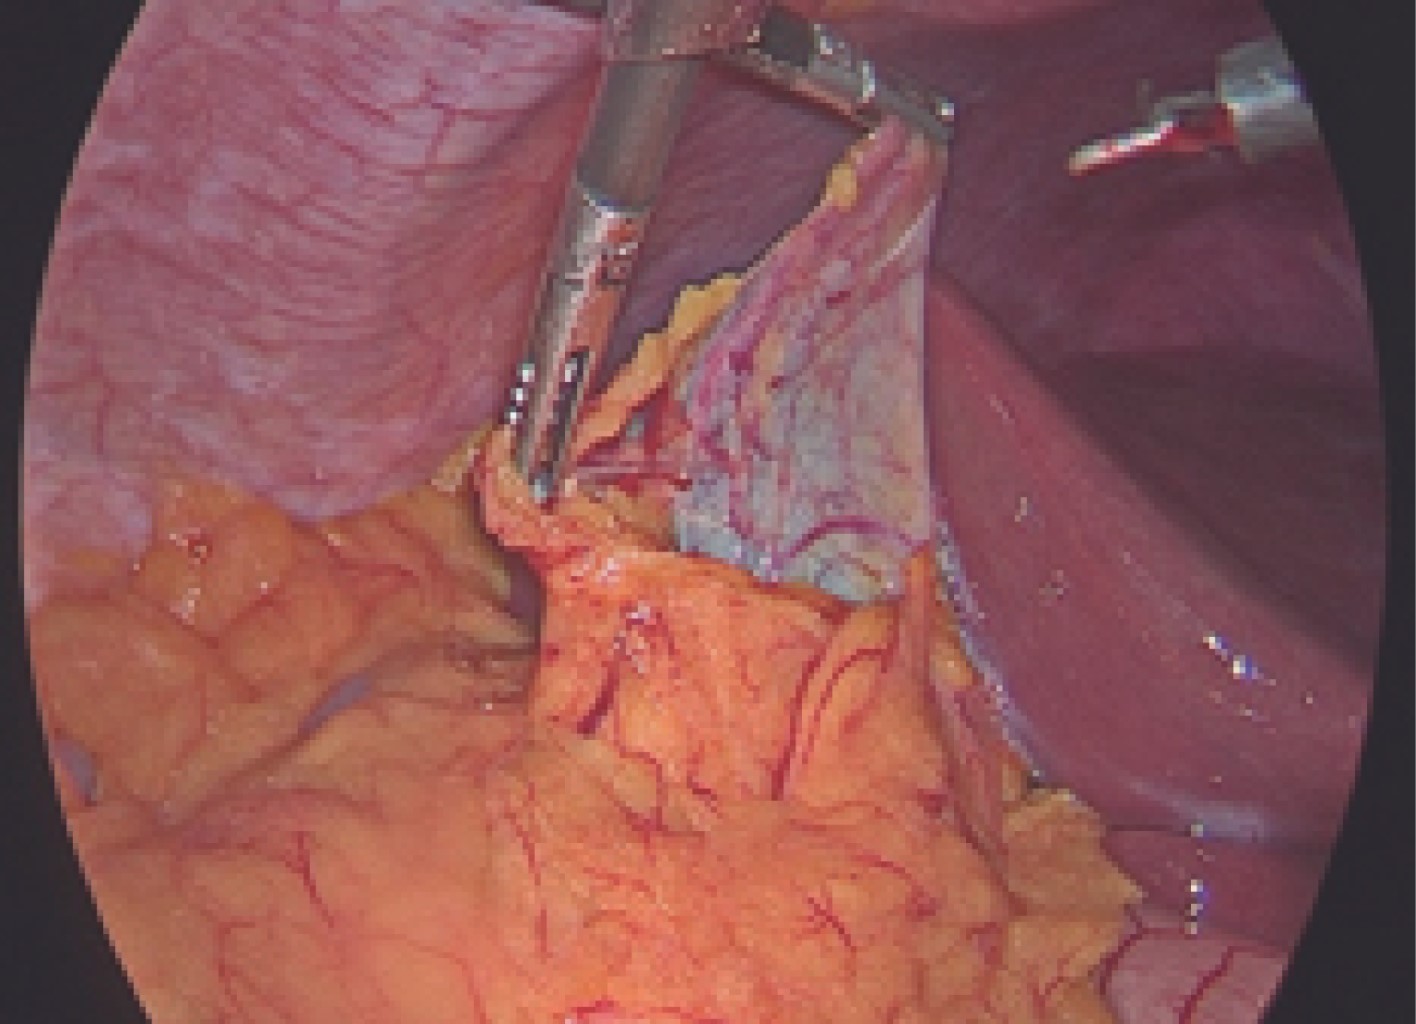

The histopathological diagnoses of the 60 operated patients were compatible with acute chronic cholecystitis and coincided with adhesions of the greater omentum, duodenum, transverse colon to Hartman's pouch, or body, or gallbladder fundus or that the greater omentum completely covered the entire gallbladder as shown in Figures 4, 5 and 6.

Figure 5